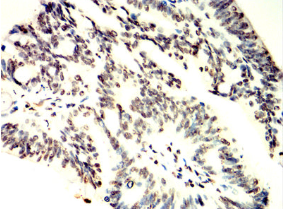

TCF7 Mouse Monoclonal antibody[1B4E9]

TCF-1

This gene encodes a member of the T-cell factor/lymphoid enhancer-binding factor family of high mobility group (HMG) box transcriptional activators. This gene is expressed predominantly in T-cells and plays a critical role in natural killer cell and innate lymphoid cell development. The encoded protein forms a complex with beta-catenin and activates transcription through a Wnt/beta-catenin signaling pathway. Mice with a knockout of this gene are viable and fertile, but display a block in T-lymphocyte differentiation. Alternative splicing results in multiple transcript variants. Naturally-occurring isoforms lacking the N-terminal beta-catenin interaction domain may act as dominant negative regulators of Wnt signaling.

Immunogen:    Purified recombinant fragment of human TCF7 (AA: 168-358) expressed in E. Coli.

IHC    1/200 - 1/1000